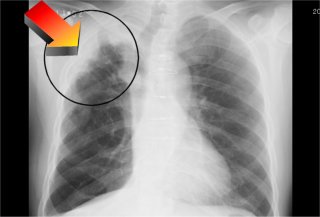

「肺がんの疑い」可能性低いと診断 |

11月に、市の定期健康診断を受けました。その結果、右肺の上部に影があり、肺がんの疑いが濃厚との見立てをもらって驚きました。慌てて築地にある国立がんセンターの門を叩きました。以来ほぼ丸2ヶ月の間、様々な検査と、薬の効きを確認する治療を受けました。

この日最終的に「がんの疑いは低い」との判定をもらい、ひとまず安心しました。来年の3月に再検査があり、それまでは執行猶予ということになります。 |